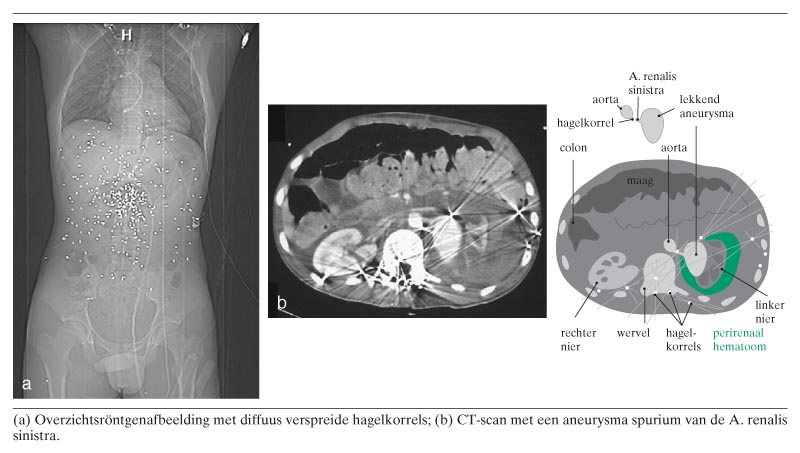

Een 15-jarige jongen belandde met schotverwondingen op de afdeling Spoedeisende Eerste Hulp (SEH). Hij was van een afstand van – naar schatting – minder dan 5 m in de rug geschoten met een hagelschotgeweer. Bij opname had hij een dubbelzijdige pneumothorax. Beeldvormend onderzoek toonde diffuus verspreid over de thorax en het abdomen talrijke (loodvrije) hagelkorrels (figuur a). Tevens bevond zich een groot aantal hagelkorrels in het spinale kanaal, met name ter hoogte van TXII tot en met LIII. Na stabilisatie op de SEH en op de intensive care volgde opname op de kinderafdeling. Gedurende…